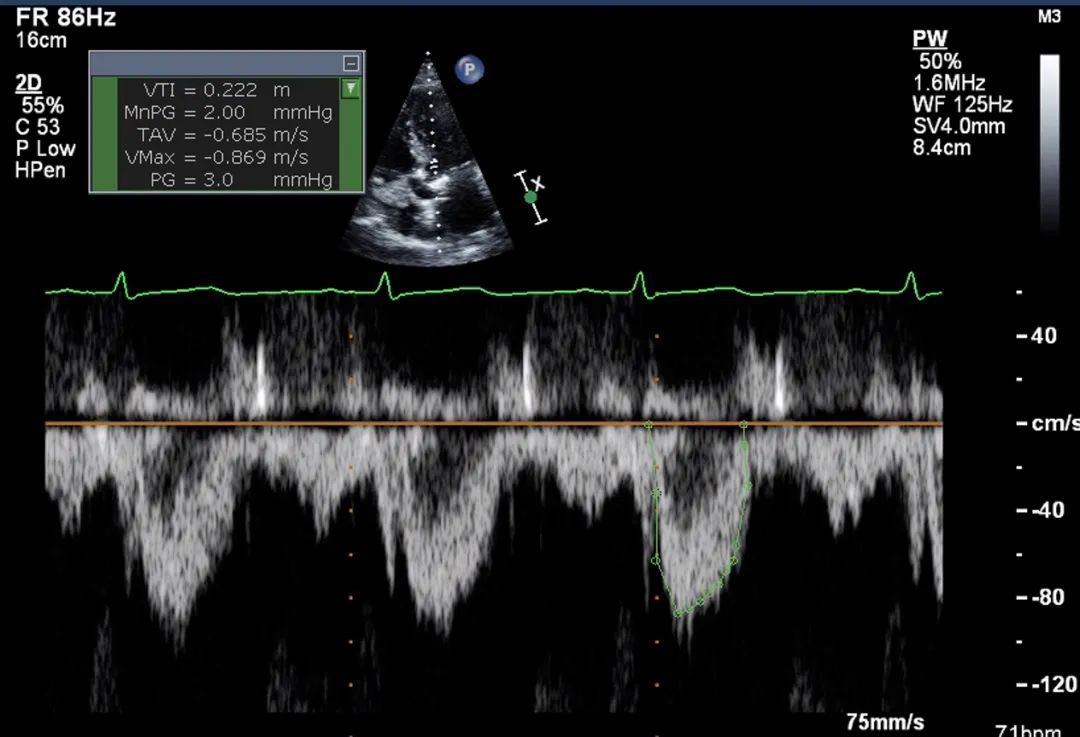

9、心尖五腔心切面: 将脉冲多普勒(pulse wave Doppler,PW)取样容积(sample volume)置于左室流出道,注意避免放置在血流汇聚区(flow convergence area)(图10)。操作时,可先将脉冲多普勒取样容积置于主动脉瓣瓣口水平,然后缓慢向心尖方向回撤至左室流出道内,直至获得无混叠且获得清晰居中的频谱多普勒波形。注意取样容积放置过于靠近主动脉瓣瓣叶,可导致高估流速;反之取样容积过于靠近心室侧,则可能低估流速。测量脉冲流速时,应应选择测量频谱波形中最明亮的白色边缘(即众数流速),代表绝大多数血细胞的流速。

图10. 心尖五腔心切面脉冲多普勒评估

心尖五腔心切面:将脉冲多普勒取样容积置于左室流出道,避免放置在血流汇聚区。